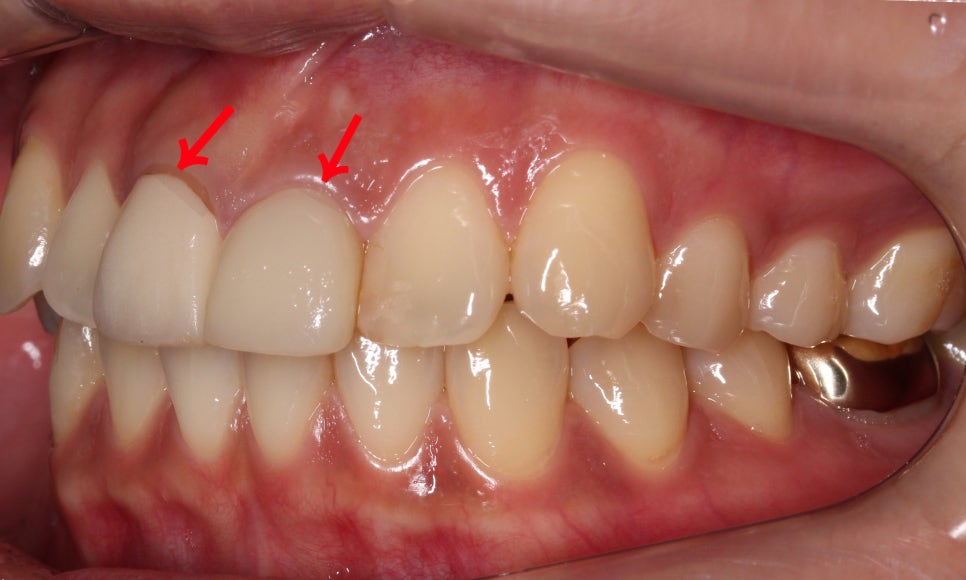

전치부의 측면 사진을 보시면

중절치의 토끼앞니 증상을

더 명확하게 확인할 수 있는데요,

특히 중절치와 잇몸 사이의 경계가

PFM크라운 치료 후 패여있는 느낌이 있어

크라운 보철의 재수복이 필요한 모습입니다.